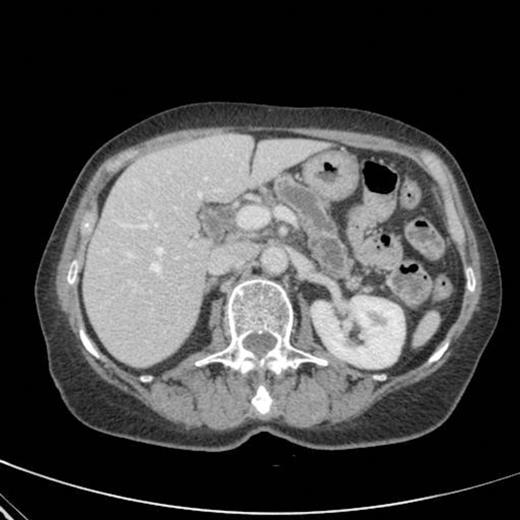

A subsequent CT scan done a year later confirmed the persistence of the gastro pancreatic fistula with polypoid herniation into the stomach and this was thought to represent main duct IPMN with mucinous tumour herniation into stomach (Fig 4). An upper GI endoscopy confirmed the gastric opening of the fistula at 50 cm on the lesser curve with a mucus plug sealing the opening (Fig 5). Biopsies were taken from around the fistulous opening and this was reported as non-specific inflammation. Again, a surgical option was offered that was declined by the patient and hence it was decided to continue with regular follow up and conservative management.